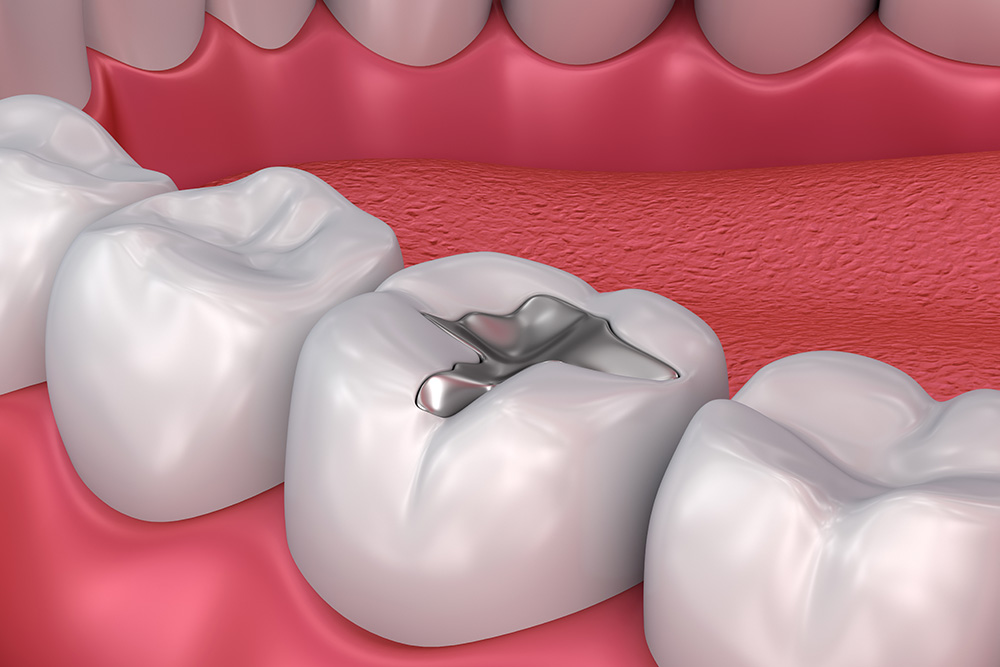

朝起きたときに顎が疲れている、強い力で噛んでしまい歯や詰め物が割れることがある方。ボツリヌス治療で咬筋の緊張を和らげることで、顎のこわばりや痛みを軽減できます。

強い噛みしめ癖により、詰め物やセラミックが欠ける方も、力のコントロールが改善されることで破損リスクを減らせます。